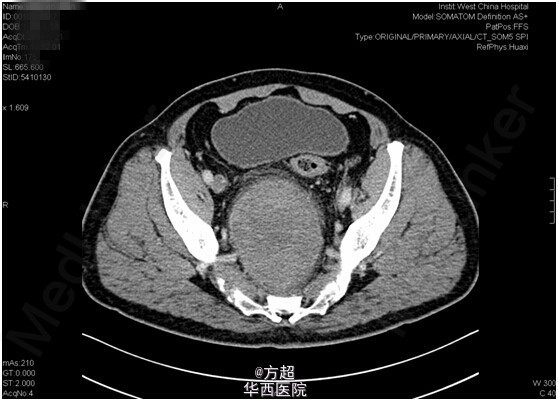

分享临床病例:盆腔巨大神经鞘瘤;中年男性,右下肢麻木、疼痛,大便习惯改变就诊,CT、MRI考虑盆腔巨大神经鞘瘤,椎管来源可能,完善术前准备后完整切除,术后病理神经鞘瘤,术后6月时随访无异常。神经鞘瘤由周围神经的Schwann鞘(即神经鞘)所形成的良性肿瘤;盆腔腹膜后神经鞘瘤较为少见,但因早期无明显症状,常因继发肢体疼痛麻木,或结直肠受压大便性状改变而就诊发现,通常包膜完整,手术完整切除为首选方案,但容易复发,且无特异性药物治疗。